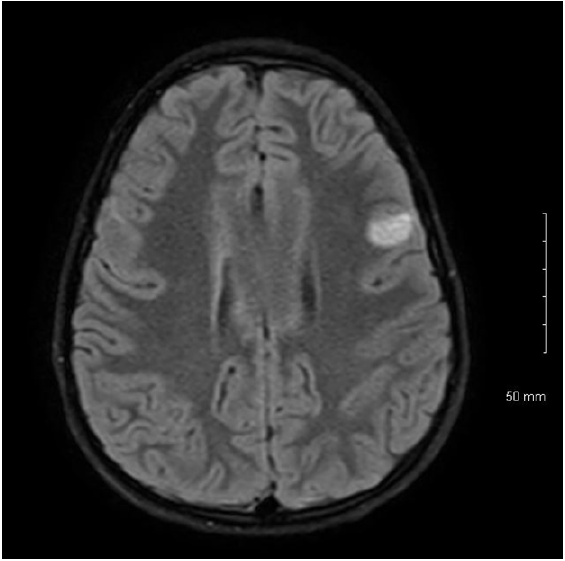

7-year-old boy presented with acute weakness following a gastrointestinal illness. Exam was notable for flaccid quadriparesis, hyporeflexia without encephalopathy. He received IVIG for presumed Guillain Barre syndrome. Initial CSF analysis and MRI Brain/spine were unremarkable except high CSF lactate of 2.9. A week later, he became less responsive, had autonomic fluctuations, lost gag reflex, and got intubated. Repeat MRI Brain showed new bilateral (L>R) cortical, subcortical and brainstem lesions as seen in Figures 1A, 1B & 1C. Serial MRI brain showed fast developing multiple lesions involving the white and gray brain matter with areas of restricted diffusion. Repeat CSF analysis including encephalopathy/ multiple sclerosis panel were unremarkable. Biopsy of left frontal lesion showed vasculitis with lymphocytic infiltration and areas of small hemorrhage with no necrosis as shown in Figures 2A & 2B. He had no response to 7 days of IV steroids or IVIG. Cyclophosphamide therapy was started for presumed CNS vasculitis and mitochondrial cocktail for high serum/CSF lactate though rest of the mitochondrial labs returned negative. Infectious work up for Aspergillus, hepatitis B&C, Bartonellosis, Lyme, Tuberculosis and HIV were negative. Investigation for Immune-mediated encephalopathy were negative for antibodies to AMPA-R, Amphiphysin, AGNA-1 to 3, CASPR2, CRMP-5, DPPX, GABA-B-R, GAD65, GFAP, LGI1, mGluR1, NMDA-R, PCA-Tr, PCA-1 & 2 in CSF and serum except mildly elevated serum anti-GAD65 (0.09 with normal <0.02). MRA head/neck and CT abdomen/chest/pelvis negative for evidence of vasculitis or mass. Two weeks later, he developed right sided focal seizures which responded to Levetiracetam, Lacosamide and Epidiolex. Whole exome sequencing confirmed pathogenic mutation for Pyruvate Dehydrogenase A1 deficiency (PDHA1). Now, 4 months later, his encephalopathy has resolved, strength and walking are improving with physical therapy.

Figure 1A: MRI Brain Flair sequence showing bilateral(left>right) hyperintense lesions of basal ganglia mainly involving Caudate and Globus Pallidi.